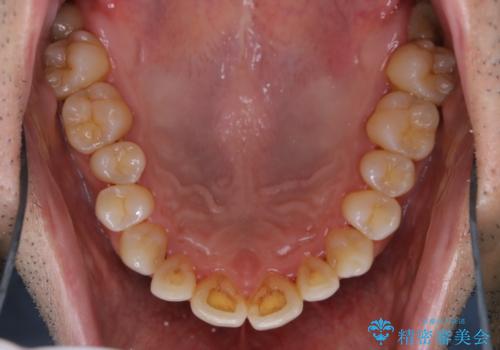

- 40年ほど歯科医院へ行ってなく、ザラつきがきになるとの事で来院されました。最近は普段の歯磨きの際、出血することがあり、歯ブラシ指導も希望されました。

お口全体に、歯垢・歯石が付着していたため、自費クリーニング(PMTC)60分コースを行い、徹底的に除去しました。

開始前

治療途中

40年ぶりの来院との事で全体的に、古くからの歯垢・歯石が硬く多く付着していたため、自費クリーニング(PMTC)60分1万円+TAXコースを行いました。

日々の磨き残しなどをそのまま放置すると、細菌が固まり硬い歯石になります。

歯石になってしまうと、とても硬く、歯ブラシで取り除くことが出来なくなります。